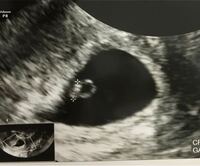

コメントトラックバック                masakohime卵黄卵黄【安心のメーカー直販】3980円以上で送料無料 当社独自のニンニクエキスをプラスした特許商品です。助産師さきの「いいママより、幸せなママになろう!」卵黄嚢が見えた!でも胎嚢は小さい6w6d心拍確認できず…でも卵黄嚢確認!f:id:tio_jobtzp:20160626100644j:image第3回 共食いも胎盤も! サメは「繁殖様式のデパート」ナショナルジオグラフィック日本版サイト画像ママと、小さな宝物♪妊娠3ヶ月 妊娠8週 9週 10週 11週 妊娠初期 の超音波写真 妊娠 出産 育児に関する総合情報サイト ベビカム画像画像f:id:sssebu:20190302010328p:plainきっといつか✧KLC 2人目妊活 胎嚢確認外でのんびり胎嚢25ミリ(胎芽、卵黄嚢なし)画像画像画像Yahoo!知恵袋妊娠7週5日。

胎のう、卵黄嚢のみ確認。胎芽未確認。